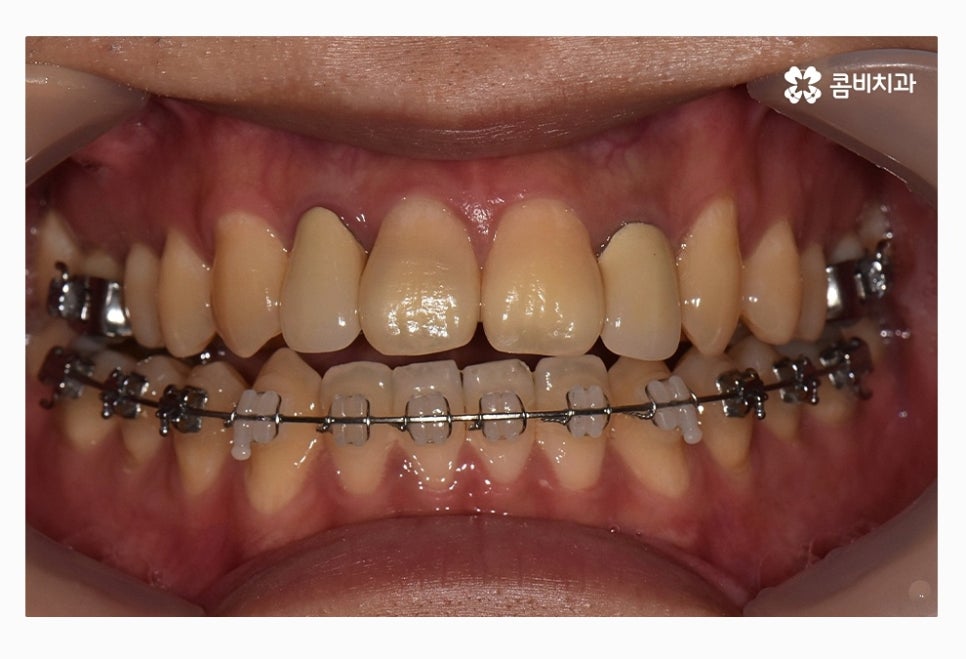

위 환자분의 경우 치열을 볼 때 정면에 비해서 측면으로 보면

앞니가 삐뚤어져 있는 것이 눈에 띄며 교합이 맞지 않아

윗니가 아랫니를 정상적으로 덮지 못하고 있는 상태이며

치아의 이동 공간 및 교합 등으로 볼 때 비발치로

치료가 가능했던 사례라고 할 수 있어요.

콤비교정이 시작된 후 사진이며 윗니는 교정 장치가 눈에 띄지

않는다는 점이 콤비교정의 특징이라고 할 수 있는데요.

평소에 입을 크게 벌리거나 크게 웃지 않는다면

외부에 교정을 하고 있다는 사실에 대해

거의 티가 나지 않을 정도로 심미성이 우수한 치료라고 할 수 있어요